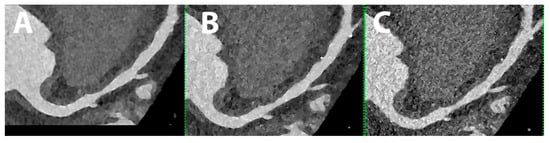

5.8. Epicardial and Pericoronary Adipose Tissue

- Mergen, V.; Ried, E.; Allmendinger, T.; Sartoretti, T.; Higashigaito, K.; Manka, R.; Euler, A.; Alkadhi, H.; Eberhard, M. Epicardial Adipose Tissue Attenuation and Fat Attenuation Index: Phantom Study and In Vivo Measurements With Photon-Counting Detector CT. AJR Am. J. Roentgenol. 2022, 218, 822–829. [Google Scholar] [CrossRef]

- Risch, F.; Schwarz, F.; Braun, F.; Bette, S.; Becker, J.; Scheurig-Muenkler, C.; Kroencke, T.J.; Decker, J.A. Assessment of epicardial adipose tissue on virtual non-contrast images derived from photon-counting detector coronary CTA datasets. Eur. Radiol. 2023, 33, 2450–2460. [Google Scholar] [CrossRef]